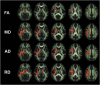

Methods: Twenty-five collegiate ice hockey players (14 males and 11 females, 20.6 ± 2.0 years), all part of the Hockey Concussion Education Project (HCEP), underwent diffusion-weighted magnetic resonance imaging (dMRI) before and after the Canadian Interuniversity Sports (CIS) ice hockey season 2011-2012 and did not experience a concussion during the season. Whole-brain tract-based spatial statistics (TBSS) were used to compare pre- and postseason imaging in both sexes for fractional anisotropy (FA), mean diffusivity (MD), axial diffusivity (AD), and radial diffusivity (RD). Pre- and postseason neurocognitive performance were assessed by the Immediate Post-Concussion Assessment and Cognitive Test (ImPACT).

Results: Significant differences between the sexes were primarily located within the superior longitudinal fasciculus (SLF), the internal capsule (IC), and the corona radiata (CR) of the right hemisphere (RH). In significant voxel clusters (p < 0.05), decreases in FA (absolute difference pre- vs. postseason: 0.0268) and increases in MD (0.0002), AD (0.00008), and RD (0.00005) were observed in females whereas males showed no significant changes. There was no significant correlation between the change in diffusion scalar measures over the course of the season and neurocognitive performance as evidenced from postseason ImPACT scores.